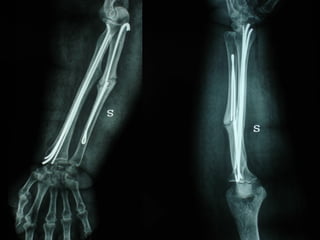

MIPPO

Dal Gennaio 2000 al Febbraio 2006 abbiamo trattato 167 fratture chiuse  con placca percutanea  in 164 pazienti :  27 lesioni diafisarie di gamba, 12 piloni tibiali ,  11 fratture prossimali di tibia, 36 fratture sovracondiloidee di femore, 17 fratture diafisarie di femore, 43 fratture metaepifisarie prossimali di omero, 21 diafisarie d’omero.  156 guarigioni 8 fallimenti

Dal Giugno 2002 al Dicembre 2004 abbiamo trattato 5 fratture esposte: 3 di tibia e 2 di ulna 5 guarigioni

I buoni risultati ottenuti dipendono da 5 punti fondamentali:   una accurata riduzione percutanea della frattura  precise vie di accesso  l’utilizzo della placca che consenta il più lungo braccio di leva possibile il pretensionamento della placca  una sintesi con un ridotto numero di viti

Accurata riduzione percutanea della frattura

Precise vie di accesso

Placche lunghe e pretensionate

Placche lunghe e pretensionate Sintesi con un ridotto numero di viti